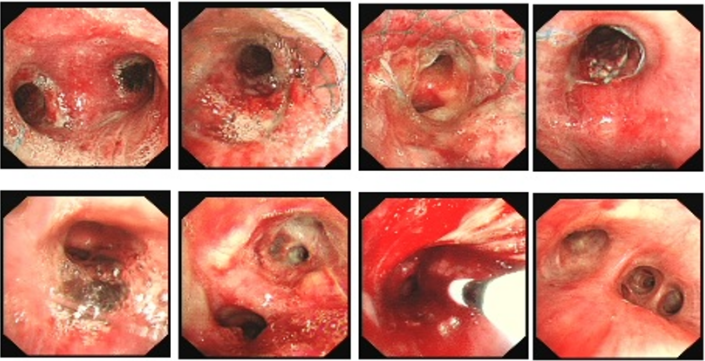

病例2:33岁,男性,全身多处淋巴结肿大1年,气促12天入院(2024年2月22日)。术前(2月22日):被动体位(前倾坐位,不能平卧),HR 136次/min,R 36次/min,SpO2 90%(FiO2 60%)。术前影像学如图24所示。紧急行气管镜检查:气管下段重度外压性狭窄,仅见缝隙,不能窥见隆突,软镜直视下置入金属覆膜支架(MTN-18/50)(图25),支架远端近隆突,术后气促明显改善。术后第4天(2月26日)咽部异物感明显,气促加重,复查胸片支架移位。再次行气管镜示:声门下腔见金属支架,经口取出支架,置入部分覆膜支架(18/40)(图26),支架远端近隆突,术后气促明显改善。B超引导下肿大淋巴结多点穿刺提示为弥漫大B淋巴瘤,后续行淋巴瘤相关治疗。病例3:64岁,女性,咳嗽、咯血、气促1个月入院(2021年12月11日)。气促明显但能平卧,HR 91次/min,R 24次/min,SpO2 94%(吸氧4 L/min)诊断未明确。外院转入。支气管镜检查:左、右主支气管内见新生物,左主混合性闭塞;右主狭窄,右中间段开口见缝隙(图27)。无外科手术指征,采取介入治疗。软镜局麻静脉镇静镇痛(咪唑安定+舒芬太尼),高频通气备用,术前使用甲基强的松龙40 mg静推,治疗策略为分步走,先处理左主,保证氧合:①左主置入导丝以备紧急情况下能快速置入支架;采用生理盐水加压注射法,支气管镜强行进入置入导丝;②充分冲洗清理左肺大量黏稠血性分泌物,防止分泌物溢出导致窒息。处理后患者氧合改善。再处理右主:①探查右中间段(缝隙),生理盐水加压注射法,支气管镜进入右中间段支气管,充分冲洗治疗;②右主支气管冻切活检(少量出血)明确诊断。下一步处理:首选Y型覆膜支架或双侧支气管支架置入,因患者诊断未明确、经济原因及考虑肿瘤的后续有效治疗,放弃Y型支架;左主混合性狭窄,仅在左主置入金属裸支架,右主新生物内镜下切除(冻切+APC)(图28)。2天后复查支气管镜, 左主支架膨胀良好, 右主及右中间支气管予以冷冻冻切残余新生物及消融后焦痂, 治疗后管腔较前进一步通畅(图29)。病例4:52岁,男性,重度呼吸困难,急诊2021年12月20日入院。气管镜检查:隆突浸润明显增宽(鳞癌),左/右主支气管重度外压性狭窄,左侧更明显(仅见缝隙)。第一步,先探查狭窄最重的左主,生理盐水加压注射进入左主,仅左主起始部重度狭窄,清理分泌物,同时置入导丝备用。第二步,探查右主,右上叶支气管基本正常,右主重度外压狭窄并右中间段开口呈缝隙,在生理盐水加压注射下支气管进入右中间段(仅右中间段起始部重度狭窄),冲洗出大量血性黏稠分泌物,置入导丝(图30)。首选Y型金属支架置入,如果没有Y型支架或缺乏置入Y型支架的技术能力,可以分别在左、右置入直筒支架。第三步:置入Y型覆膜支架(图31),使用刘志光改良的Y型支架置入装置(专利),软镜置入快捷(耗时10 min)。支架规格:18/40-14/30-14/20(右)。置入后,支架膨胀良好,呼吸困难显著改善。